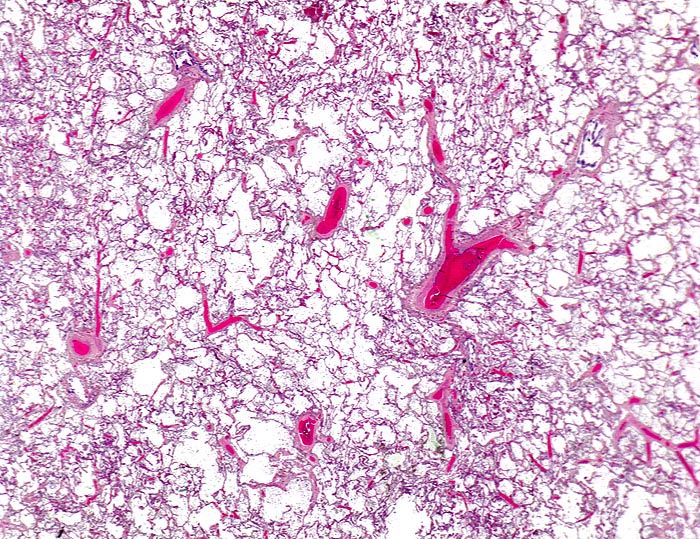

chronische Lungenstauung: Venulosklerose

Starke Blutfülle der Alveolarsepten. Die angeschnittenen Venen zeigen eine deutliche Wandverdickung.

Patient mit koronarer Herzkrankheit und Linksherzinsuffizienz.

Venen sind im Lungenparenchym daran erkennbar, dass sie im Gegensatz zu den Arterien nicht in unmittelbarer Nachbarschaft eines Bronchus liegen. Die Wanddicke einer normalen Pulmonalvene beträgt maximal 5% des Gefässdurchmessers.